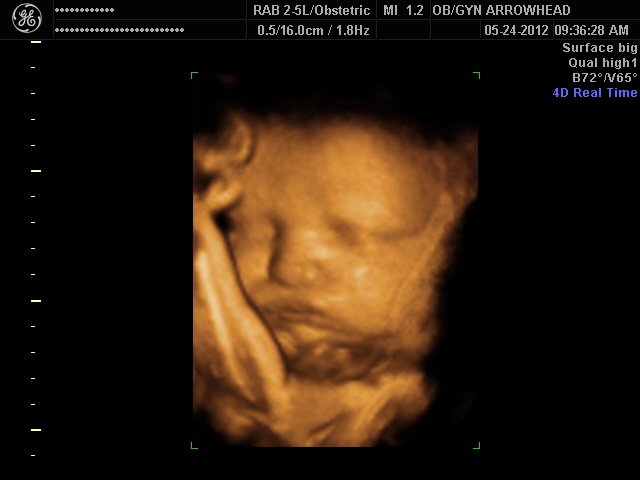

We offer complimentary 3D/4D Ultrasounds to all our OB patients around 30 weeks! The following photos are some examples of our work, shown with permission from our patients.